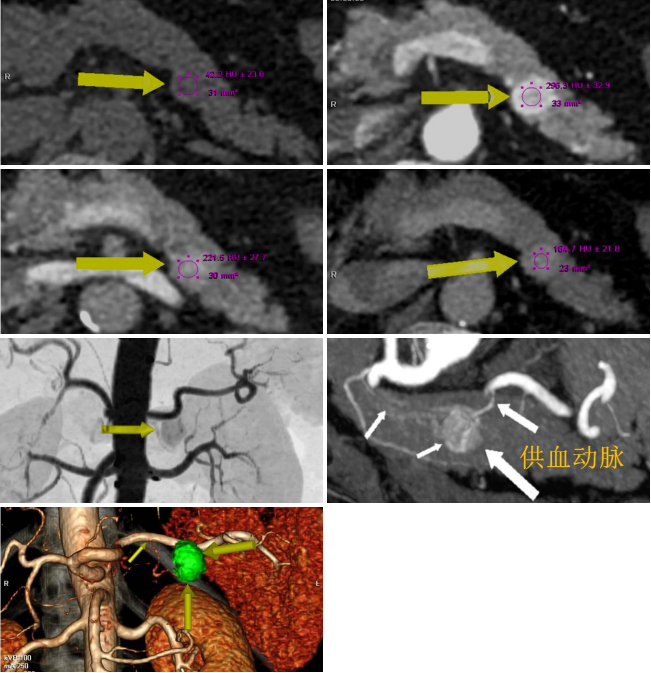

病例二 女,63歲,以持續(xù)性腹部疼痛不適半天就診。既往有冠心病15年、心房纖顫史5年余;高血壓5年。

采用心臟+主動(dòng)脈血管一站式檢查,可見(jiàn)該患者腸系膜上動(dòng)脈及其分支充盈缺損,同時(shí)顯示左心耳內(nèi)多發(fā)血栓, 隨時(shí)有血栓脫落的危險(xiǎn)。

全麻下行剖腹探查、 腸系膜上動(dòng)脈血栓取出術(shù), 病理顯示血栓樣組織機(jī)化。

患者術(shù)后第三天,由于右側(cè)肢體活動(dòng)障礙,語(yǔ)言受限,急查CT發(fā)現(xiàn)多發(fā)腔隙性腦梗塞,MRI檢查后明確左側(cè)急性梗死。

腸系膜上動(dòng)脈栓塞栓子多來(lái)源于心臟,也可來(lái)自于主動(dòng)脈壁粥樣硬化斑塊脫落。腸系膜上動(dòng)脈從腹主動(dòng)脈分出,主干口徑又較大,脫落的栓子易于進(jìn)入,在血管狹窄或分叉處導(dǎo)致血管栓塞。

臨床表現(xiàn)主要有“Bergan三聯(lián)征”1 、劇烈而沒(méi)有相應(yīng)體征的腹痛。2器質(zhì)性心臟病和并發(fā)心房纖顫的心臟病。3、胃腸排空障礙表現(xiàn)如腹瀉、 血便。

640層寬體探測(cè)器CT掃描速度快,可進(jìn)行大范圍心血管一站式檢查,快速排除血管病變,且由于探測(cè)機(jī)單元只有0.5mm,對(duì)于一些微小的病變也能清晰顯示。